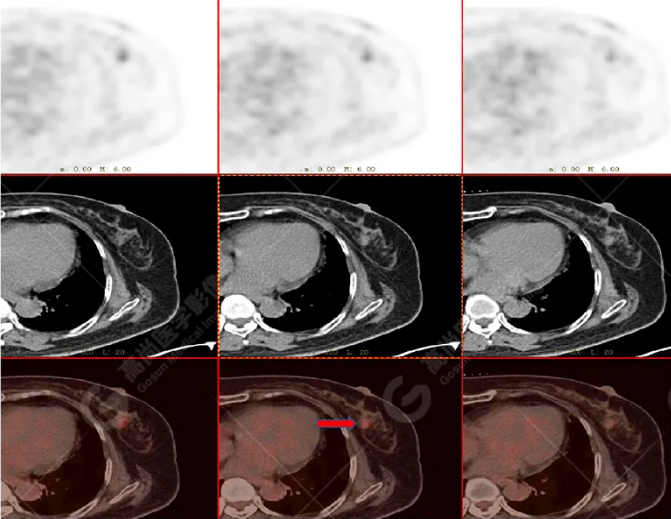

PET/CT影像圖

胸椎溶骨性骨質(zhì)破壞,F(xiàn)DG環(huán)狀代謝增高,SUVmax為4.0。

左側(cè)乳腺一軟組織結(jié)節(jié),F(xiàn)DG代謝增高,SUVmax為2.6。

最終診斷:左側(cè)乳腺癌伴胸椎單發(fā)骨轉(zhuǎn)移。